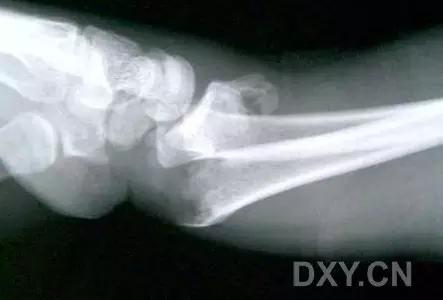

6. Bennett 骨折

第 1 掌骨基底的斜形骨折,掌骨近端形成轴向移位,掌侧边缘形成三角形的骨碎片。

(来源:Radiopaedia)